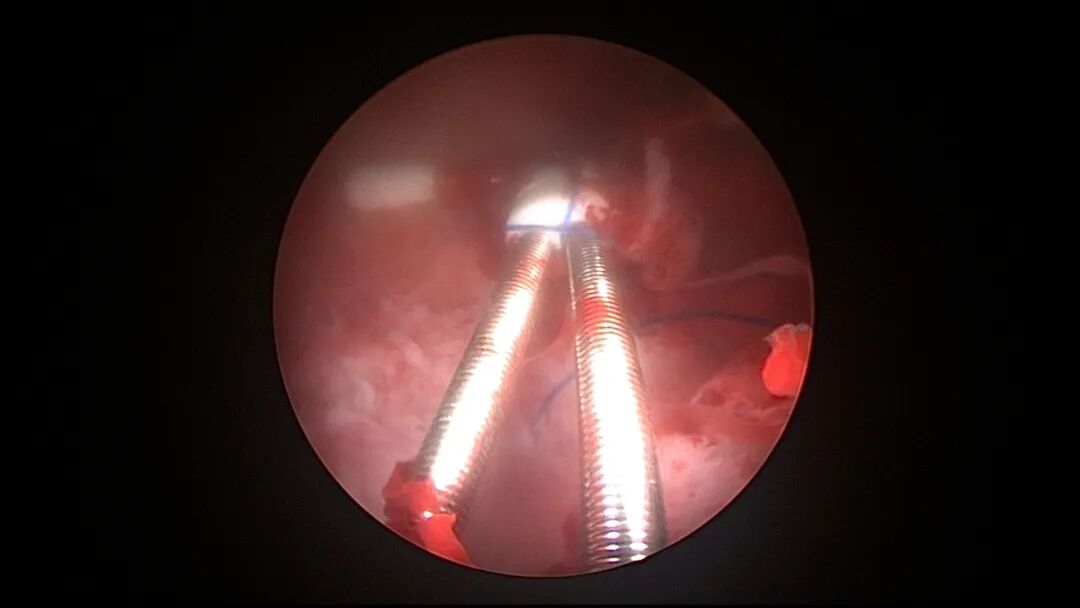

操作步骤描述:宫腔检查镜可完成操作,扩张宫颈至7号扩宫棒,检查镜能轻松通过,避免镜鞘与节育环纵臂在宫颈管形成卡压及筷子效应,影响操作,或卡压摩擦阻力大带出节育环。可用单级电针在宫底扎出小凹坑做标记或作为置入挂钩的隧道(不是必须的)。将挂钩用异物钳直视下送入宫腔,或用中弯钳盲视下送入宫腔,异物钳夹持挂钩将倒钩端插入宫底肌层,越过倒钩。用环尾丝或不可吸收线在节育环顶端打结,形成一个线圈,直径约0.5cm~1cm,结打在线圈旁边,便于夹持操作。将环装回推杆送入宫腔,再夹住节育环固定线圈抵紧宫壁稍旋转就可以将线圈滑进挂钩缺口,挂到挂钩上,可再次向宫底推送挂钩少许,不必夹闭挂钩缺口,重力作用和内膜生长都会阻止线圈脱出,可以用电针电凝挂钩周围组织,进一步防止挂钩脱落。异物钳原位固定节育环,退出宫腔镜,距宫颈外口0.5cm~1cm剪断剩余尾丝。宫颈扩张到9号扩宫棒,冷刀系统异物钳夹持挂钩及线圈也可完成以上操作。

单级电针标记挂钩位置

取胚术后丝线挂钩固定节育环图片及视频

子宫腺肌症内膜息肉切除后丝线挂钩固定曼月乐并电凝图片及视频

异常子宫出血内膜增生节育环尾丝挂钩固定曼月乐图片及视频